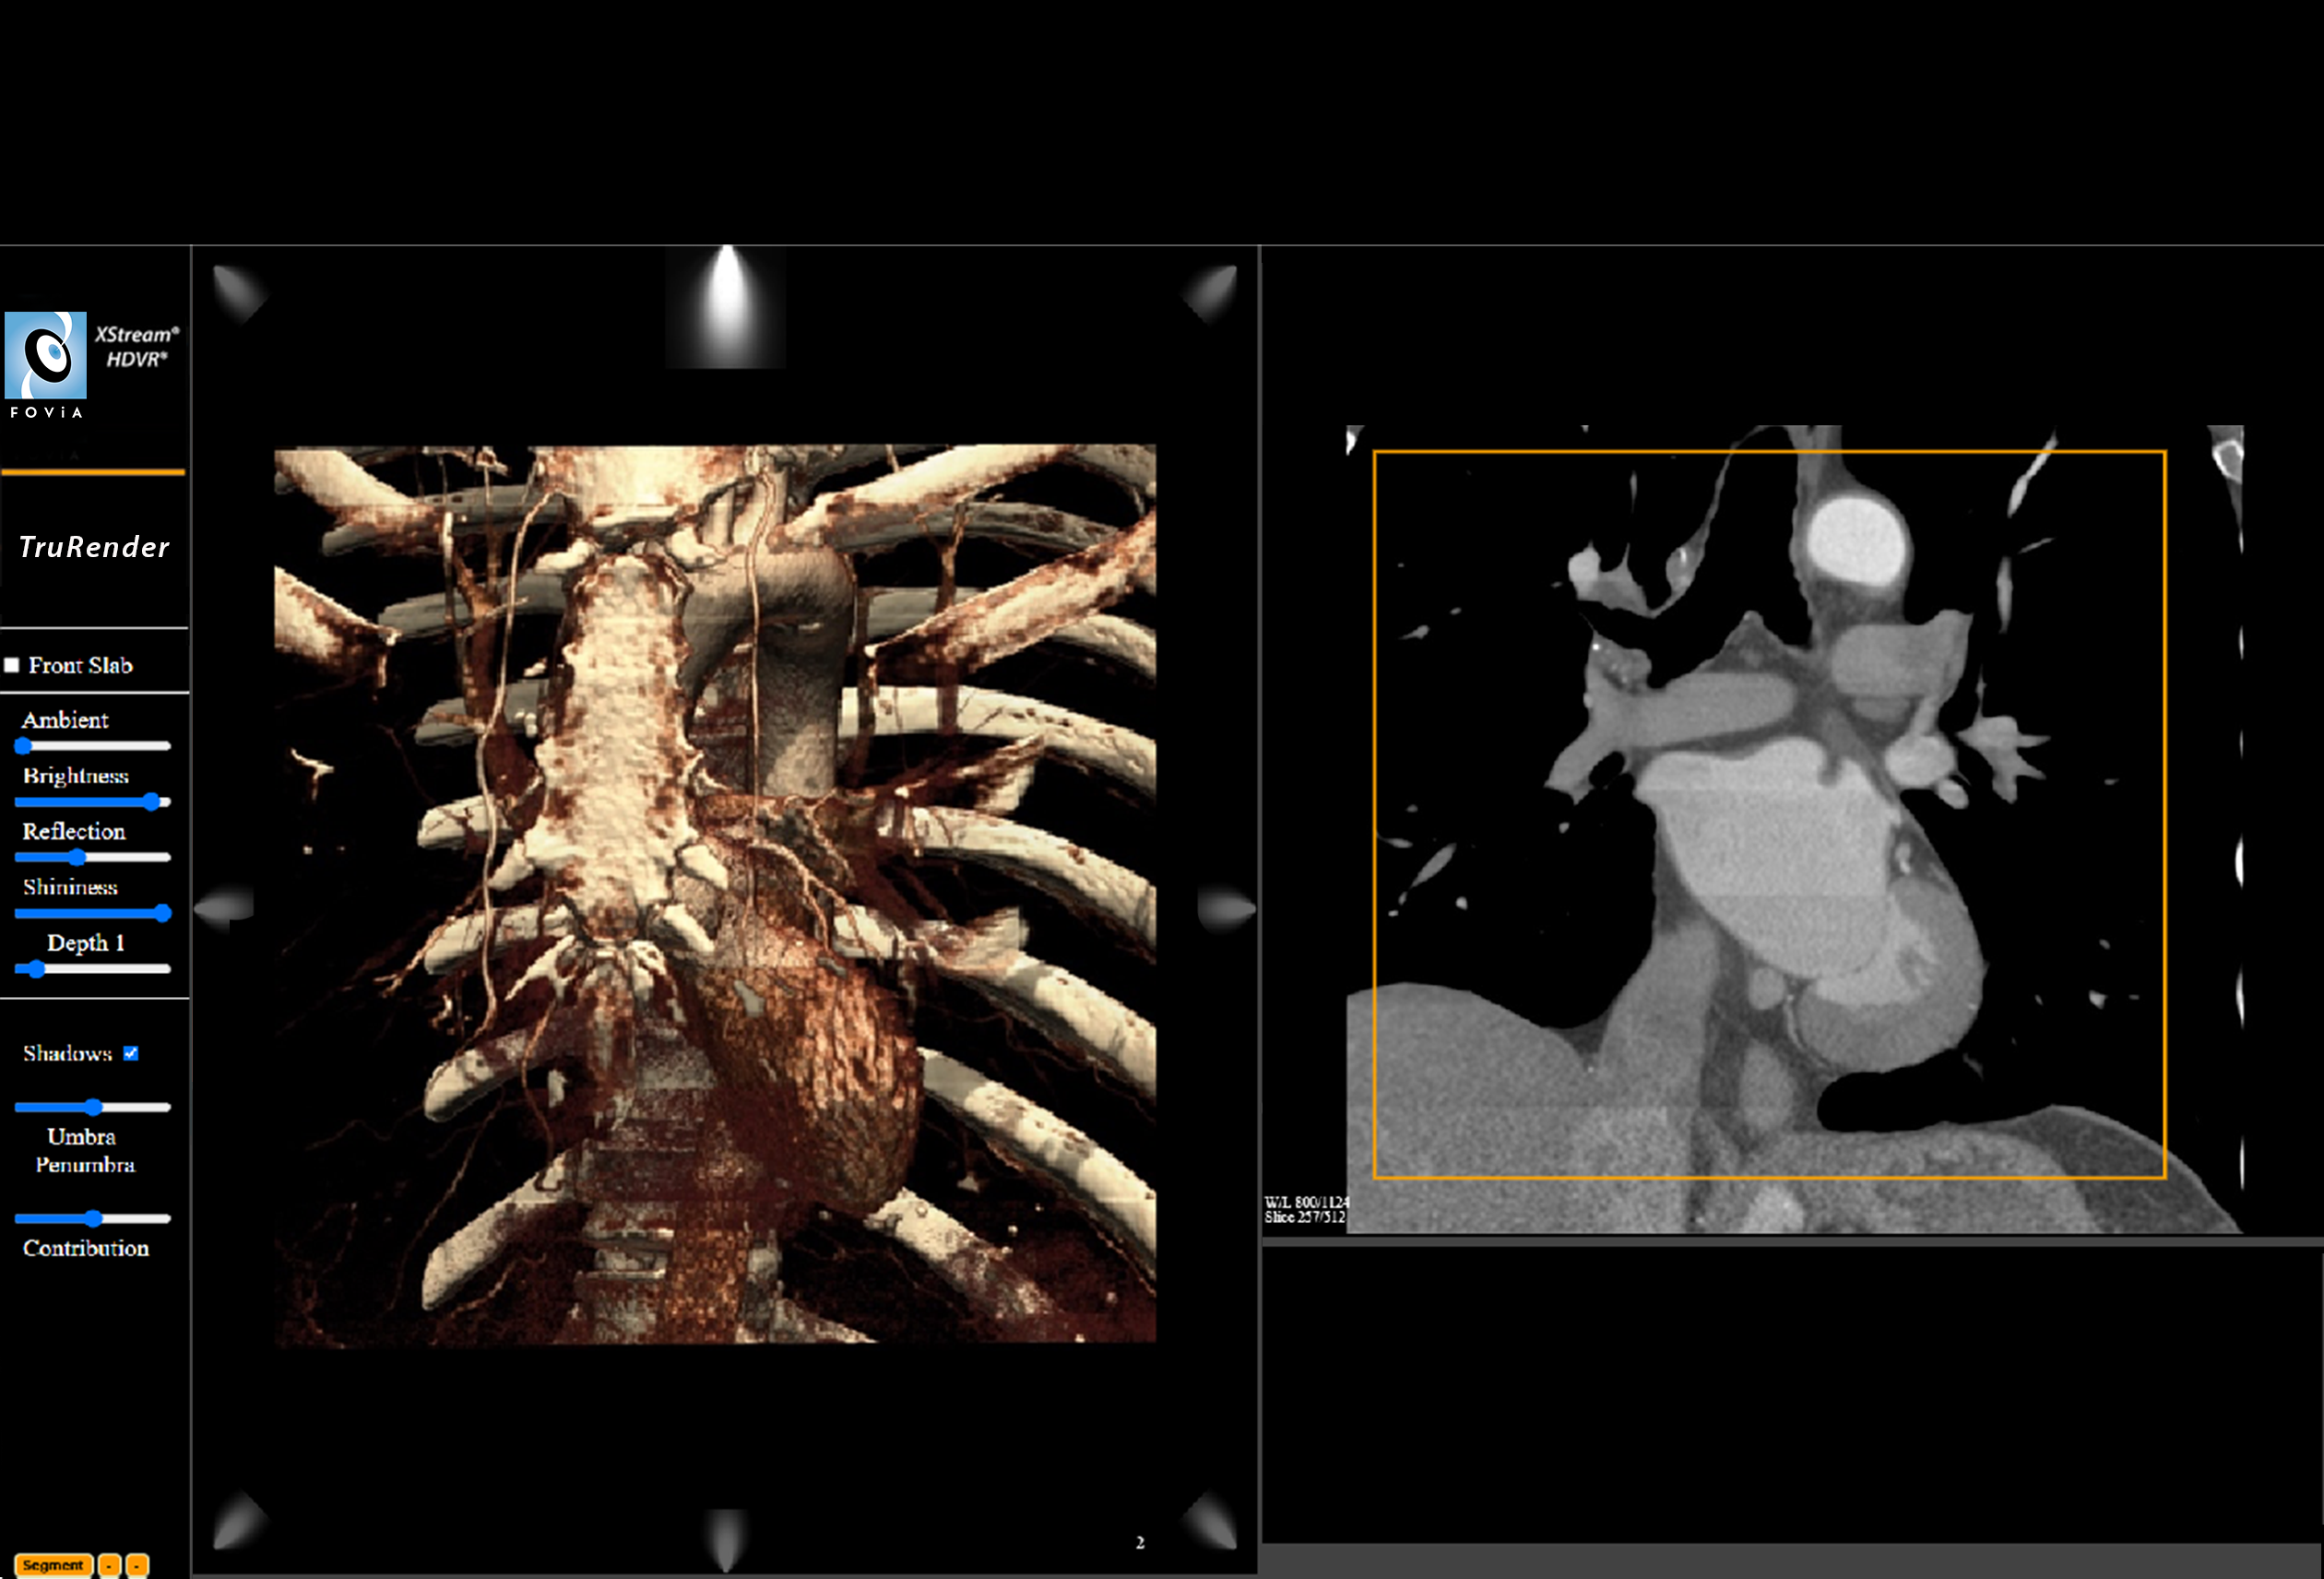

TruRender

F.A.S.T. 3D Print Cardiac Workflow

TruRender